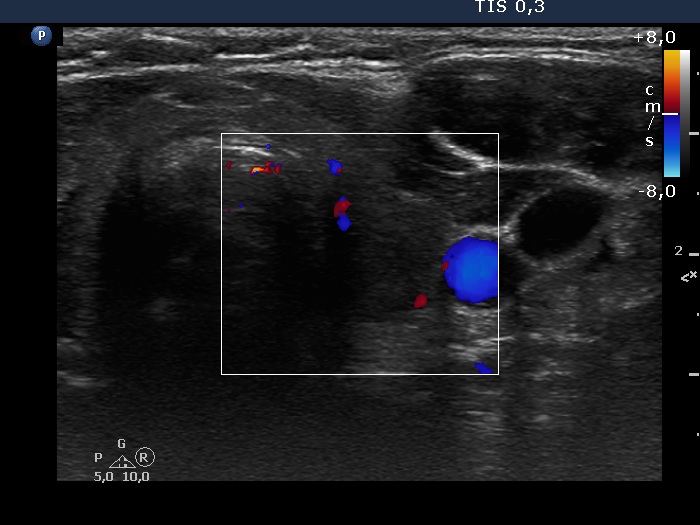

Clinical presentation: A 55-year-old woman was referred for follow-up investigation. She has been treated for hypothyroidism for five years.

Palpation: Both lobes were moderately firm and uneven.

Hormonal investigation: euthyroidism on daily 75 microgram levothyroxine (TSH 1.28 mIU/L). The aTPO level was 296 U/mL 7 years ago.

Ultrasonography revealed minimally-moderately hypoechogenic thyroid presenting more hypoechogenic areas. These corresponded to more active foci of Hashimoto's thyroiditis and not to nodules in a pathological sense.

Suggestion: to continue with the same dose of replacement therapy.